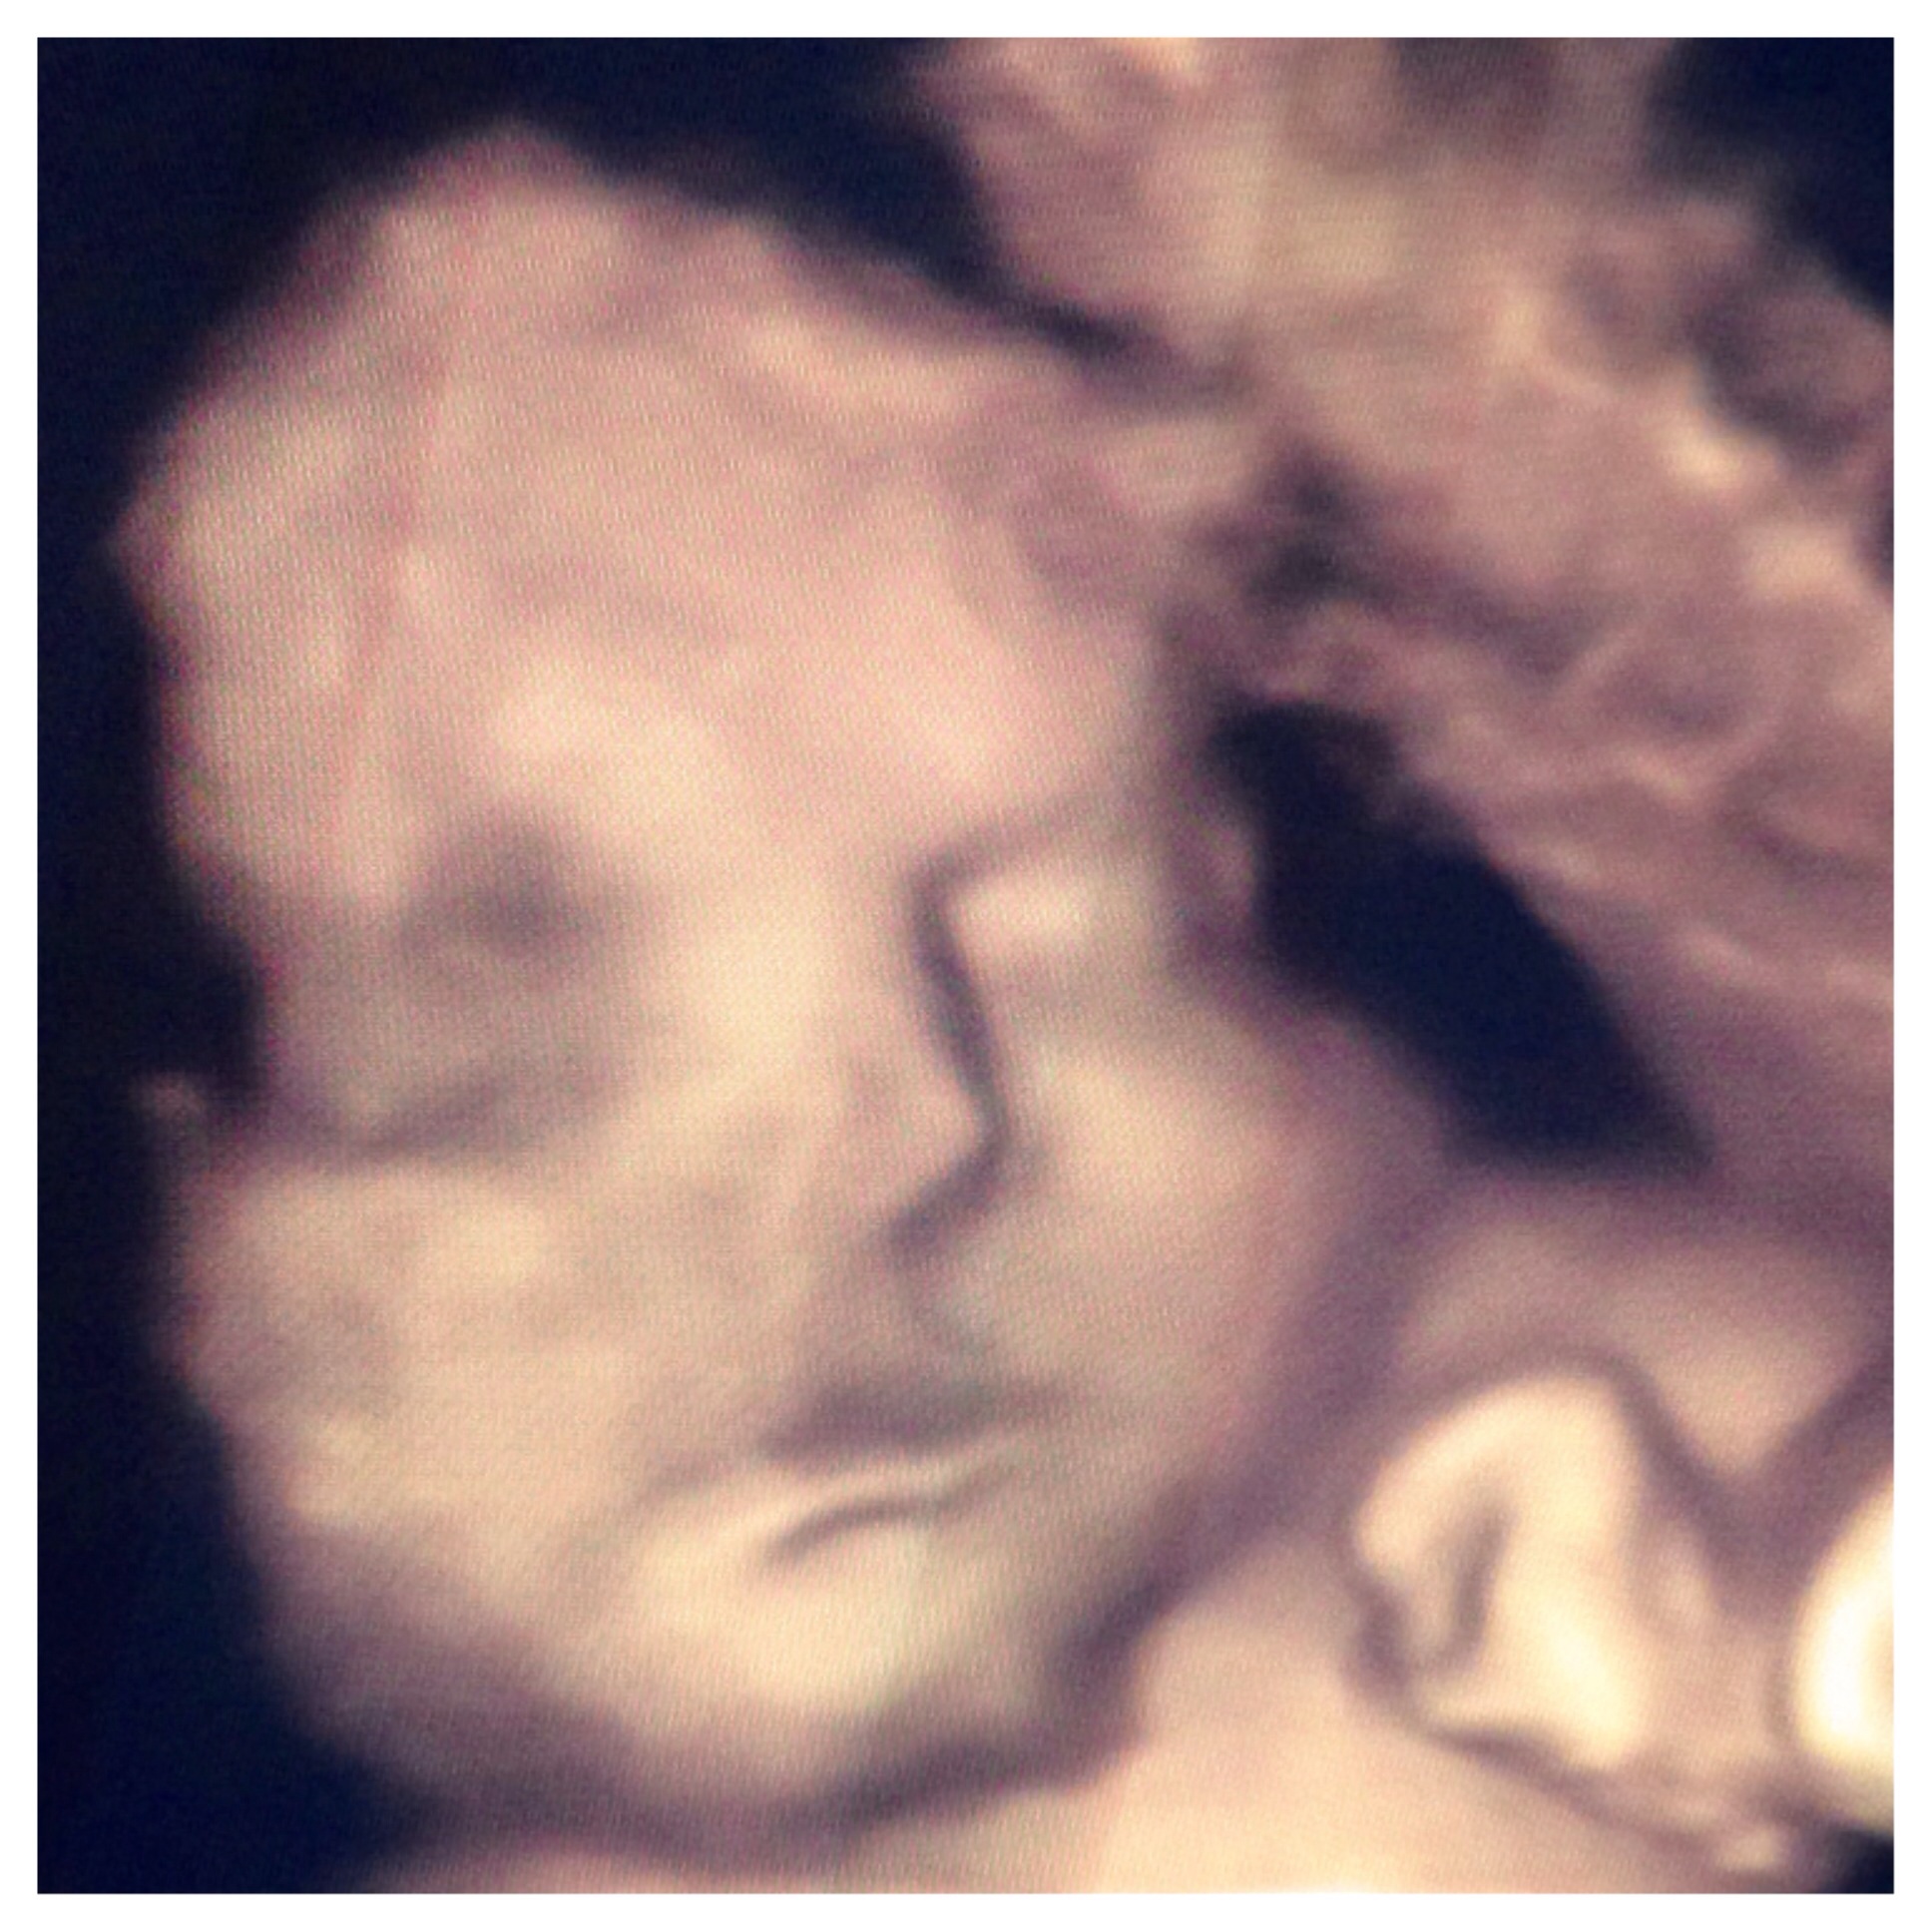

Just left the doctor. I'm 30weeks 2days. Baby is measuring 3 weeks ahead. Weighing in at 4.7 pounds, his head is equally as large. That puts him in the 81% on the growth chart. But cervix looks good at 4.4 and we are both healthy. Hopefully he keeps baking in there till June 6th! I can't believe how chubby his cheeks are already!